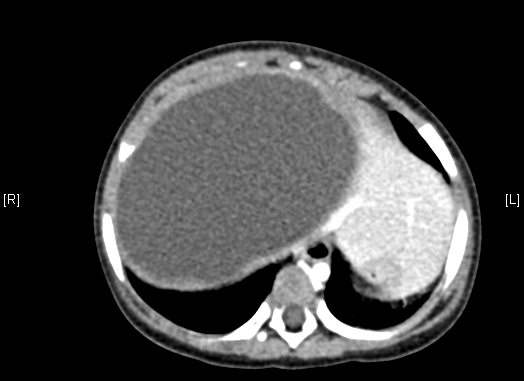

上腹部增强CT:肝右叶囊实性占位。上腹部增强CT示间叶性错构瘤。

术前CT检查:

动脉期